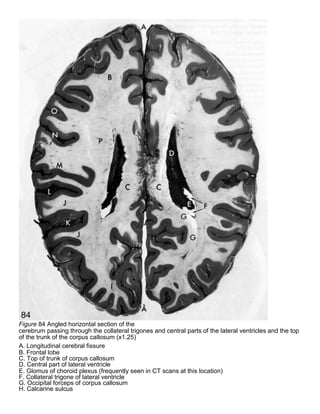

Figure 84 Angled horizontal section of the

cerebrum passing through the collateral trigones and central parts of the lateral ventricles and the top

of the trunk of the corpus callosum (x1.25)

A. Longitudinal cerebral fissure

B. Frontal lobe

C. Top of trunk of corpus callosum

D. Central part of lateral ventricle

E. Glomus of choroid plexus (frequently seen in CT scans at this location)

F. Collateral trigone of lateral ventricle

G. Occipital forceps of corpus callosum

H. Calcarine sulcus

I. Occipital lobe

J. Temporal lobe

K. Superior temporal sulcus

L. Lateral sulcus

M. Parietal lobe

N. Central sulcus

O. Precentral sulcus

P. Corona radiata

Figure 84 Angledhorizontal section of the cerebrum passing through the collateral trigones and central parts of the lateral ventricles and the top of the trunk of the corpus callosum (x1.25) A. Longitudinal cerebral fissure B. Frontal lobe C. Top of trunk of corpus callosum D. Central part of lateral ventricle E. Glomus of choroid plexus (frequently seen in CT scans at this location) F. Collateral trigone of lateral ventricle G. Occipital forceps of corpus callosum H. Calcarine sulcus

I. Occipital lobe J.Temporal lobe K. Superior temporal sulcus L. Lateral sulcus M. Parietal lobe N. Central sulcus O. Precentral sulcus P. Corona radiata